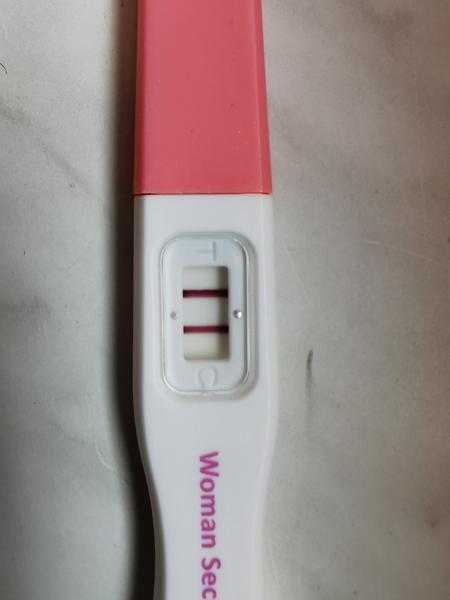

A v hlave miliarda otáznikov... ako je toto možné po tomto? : (fotka)

Ale evidetne ani // koľajnice nezaručujú istotu víťazstva😢😢

@mey8 to mi je ľúto 🙁 hcg v krvi ešte nezaručuje kvalitu plodu... Ani to či je v maternici, pri mimomaternicovom ti tiež test ukáže 2 čiarky. Veľmi ma to mrzí. Ja som raz potratila a tak som sa teraz netešila pokiaľ som nevidela bit srdiečko. A celý prvý trimester je kolotoč. Nabudúce sa podarí netreba sa vzdávať ❤️☘️ tie čiarky ti ukazuje lebo máš stále hcg v krvi. Čo ti povedal lekár dnes?

@milakrasna praveže pri prvom som mala vždy len sušíka, takú slabú čiarku a dotiahli sme to do 8 tt, tak som si (án, viem, naivne) myslela, že pri takýchto koľajnicia a potvrdení dr. že plod je tam kde má byť, že to spolu dotiahneme qž do náručia😢😢 teraz sa vôbec bojím otehotnieť, že čo zasa.....:(

Ahojte chcela by som sa Vás spýtať som 8 deň po Ket a vyšiel mi takýto tt. Nie je to príliš veľa týždňou na to ze som len 8 deň po ket? 5 dňovej blastocysty. Asi len zbytočne rozmýšľam mam za sebou 2 ivf a toto je môj 5 vklad... Nikdy som nemala také silné testy tak skoro...

No baba bláznivá keď su slabé je zle keď sú silné je zle 😂.

@vitka12 môže ti kľudne ukazovať 🙂 ja som na 8den po KET mala kolajnicu a 6den po Ket slabú čiarku a na krvi som mala krásnych 2400hcg 🙂 a teraz som v 15tt zatiaľ úspešne 🙂 takze všetko je v poriadku

Na foto moj test 8 den po vklade ten úplne dolu 🙂

@petruska21 ďakujem za odpoveď tak hádam to bude všetko v poriadku 🙂a to si veru mala riadnu koľajnícu 😀

@vitka12 určite to bude v poriadku držím palce ✊ a v 10 den už úplnú ešte silnejšiu ako kontrolná :D

@petruska21 Wau pekná koľajnícka na 8 dnik...